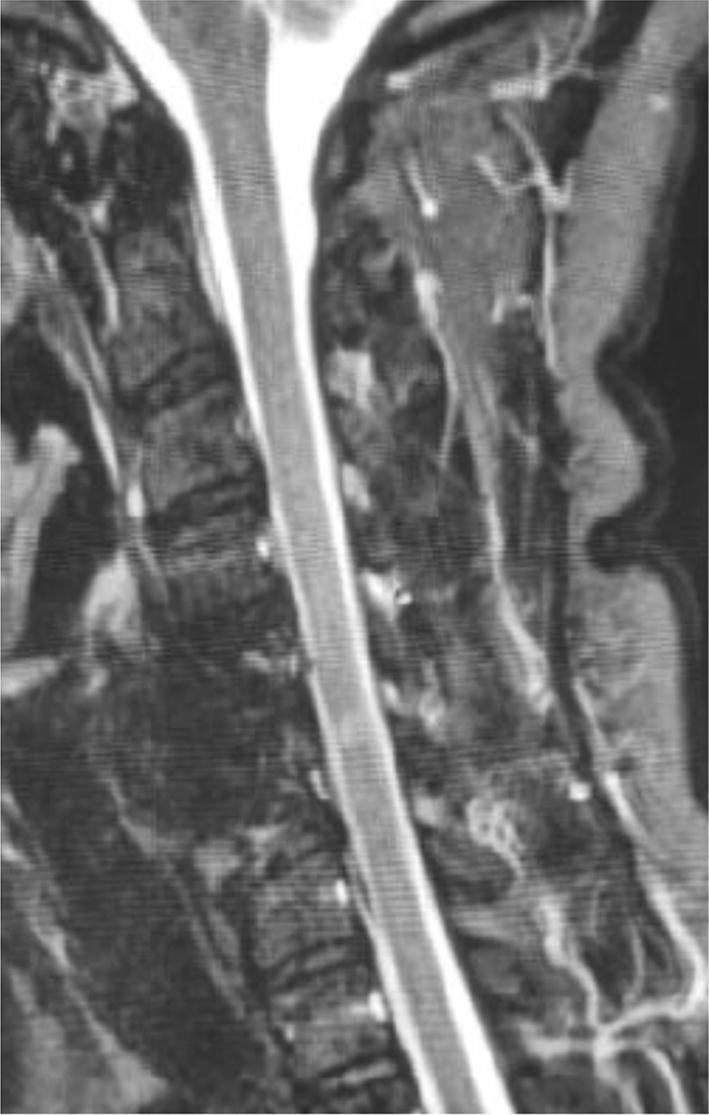

The association between coronaviruses and central nervous system (CNS) demyelinating lesions has been previously shown. However, no case has been described of an association between the novel coronavirus (SARS-COV-2) and CNS demyelinating disease so far. SARS-COV-2 was previously detected in cerebrospinal fluid (CSF) sample of a patient with encephalitis. However, the virus identity was not confirmed by deep sequencing of SARS-COV-2 detected in the CSF. Here, we report a case of a patient with mild respiratory symptoms and neurological manifestations compatible with clinically isolated syndrome. The viral genome of SARS-COV-2 was detected and sequenced in CSF with 99.74-100% similarity between the patient virus and worldwide sequences. This report suggests a possible association of SARS-COV-2 infection with neurological symptoms of demyelinating disease, even in the absence of relevant upper respiratory tract infection signs.

先前已经表明冠状病毒与中枢神经系统(CNS)脱髓鞘病变之间存在关联。然而,迄今为止,尚未有新型冠状病毒(SARS-COV-2)与 CNS 脱髓鞘疾病相关的病例描述。先前在患有脑炎的患者的脑脊液(CSF)样本中检测到了 SARS-COV-2。但是,通过对 CSF 中检测到的 SARS-COV-2 进行深度测序,并未确认病毒的身份。在这里,我们报告了一例轻度呼吸道症状和与临床孤立综合征相吻合的神经系统表现的患者。在 CSF 中检测到了 SARS-COV-2 的病毒基因组,并进行了测序,患者病毒与全球序列之间的相似度为 99.74-100%。该报告表明,SARS-COV-2 感染可能与脱髓鞘疾病的神经症状有关,即使在上呼吸道感染的相关迹象不存在的情况下也是如此。